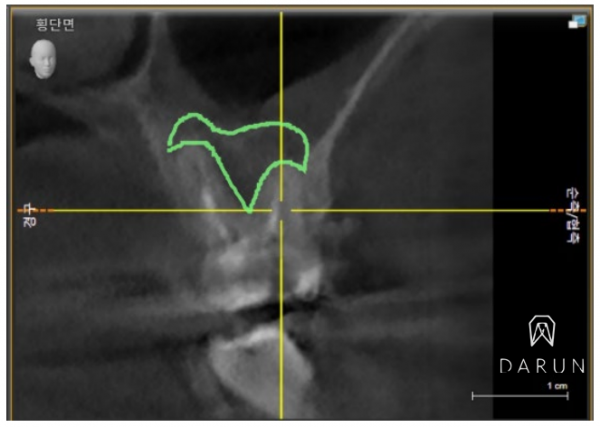

CT 사진입니다.

표시한 이부분이 전부다 염증이에요..

뿌리사이에 저렇게 광범위하게 진행된 것 같아요.

저렇게 까지 악화된 경우엔 예후가 안 좋을 수 있어요..